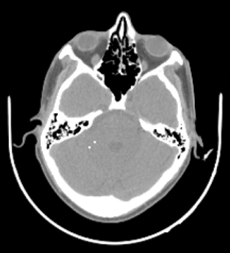

Online Calibration of Noncircular Orbits based on Preoperative CT: Accurate geometry calibration is essential for cone-beam CT reconstruction, particularly on C-arm scanners where pre-calibrated geometry is often unavailable due to irregular scan trajectories, mechanical jitter, and patient motion [6, 13]. In this experiment, we acquired 360 projections of an anthropomorphic head phantom (The Phantom Laboratory, Greenwich NY) using a sinusoidal gantry trajectory, emulated by hexapod stage on an X-ray test bench with a maximum tilt angle of 10°. The calibration framework with 6 DoF described in Ref.[6] was employed for calibration and reconstruction. Specifically, each projection was registered to a preoperative volume 𝝁ref\boldsymbol{\mu}_{ref} using the differentiable forward projector and NCC loss: